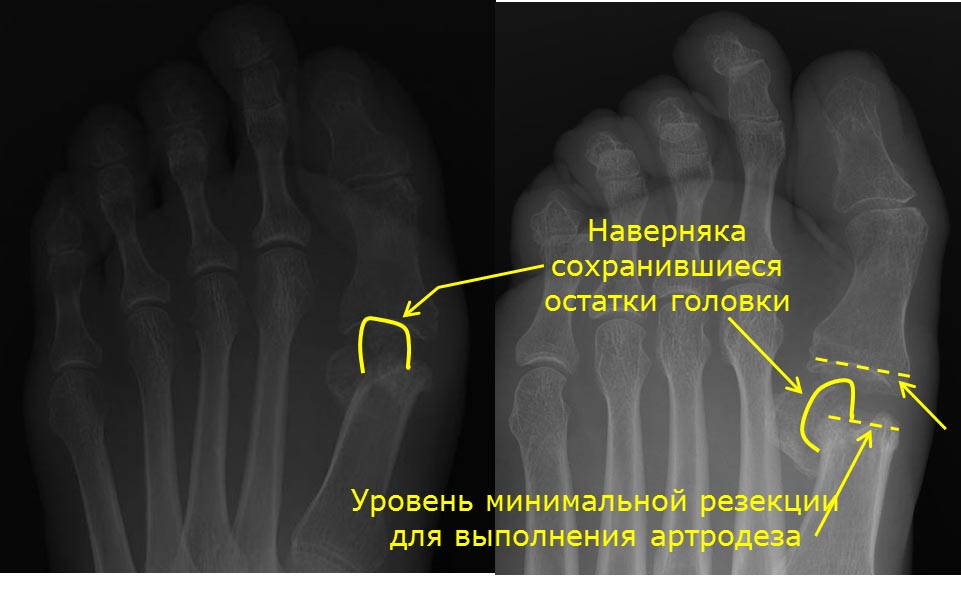

Причина центральной метатарзалгии в данном случае очень понятна, так же

как и то, что нужно делать по этому поводу: любые укорачивающие и

поднимающие головки М2-3 (4?) остеотомии. Но автор поста написал о болях

в суставе большого пальца. Для меня причина этой боли непонятна.

Соответственно, и что делать по данному поводу неясно. Говорить, что у

пациентки полностью отсутствует головка М1 мы не можем. Во вложении я

обрисовал то, что точно осталось от головки. Но в каком положении

находится этот фрагмент и насколько он велик, и есть ли еще остатки

головки, без рентгенограммы в боковой проекции или КТ я не знаю.

Предположим, что будет выполнен артродез. Если для его выполнения

резецировать остатки головки, то при таком большом расстоянии между М1 и

основной фалангой, как сейчас, даже установка между артродезируемыми

поверхностями трансплантата толщиной 1 см приведет к еще большему

укорочению первого луча. Избавит ли такой артродез пациентку от болей?

Очень сомневаюсь. Потому что не понимаю, чем анкилоз ПФС1 будет лучше

представленного на снимках состояния. К сожалению, без дополнительной

информации дальнейшее обсуждение данного случая потеряло смысл.